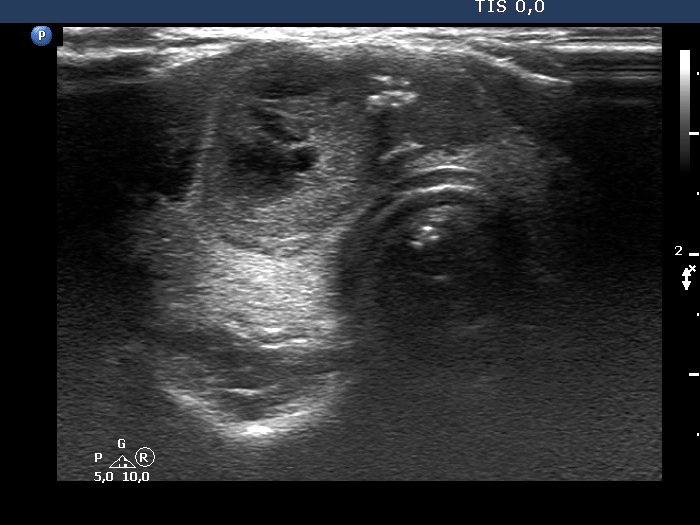

One year after the first examination (second row of images):

Clinical presentation. The patient had no complaints.

Palpation: unchanged.

Hormonal evaluation: TSH 0.91 mIU/L.

Ultrasonography. The cystic areas of the nodule in the isthmus have increased. The lesion presented more bright echogenic lines and granules which corresponded to figures caused by posterior back wall enhancement.